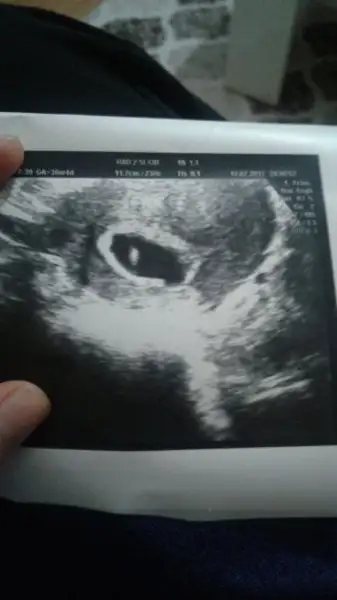

5 cm i gecmis otekilerde ne yaziyoduEki Görüntüle 2022081 Eki Görüntüle 2022082 5+6 ydi 6+2olms

crl yazan altta crl boyunu gosteriyo ordada 5.3 yaziyo cok bulanik cm gibi gordmHangi yazıya bakiyon

Him önceden 0.28 mm di şimdi 0.53crl yazan altta crl boyunu gosteriyo ordada 5.3 yaziyo cok bulanik cm gibi gordm